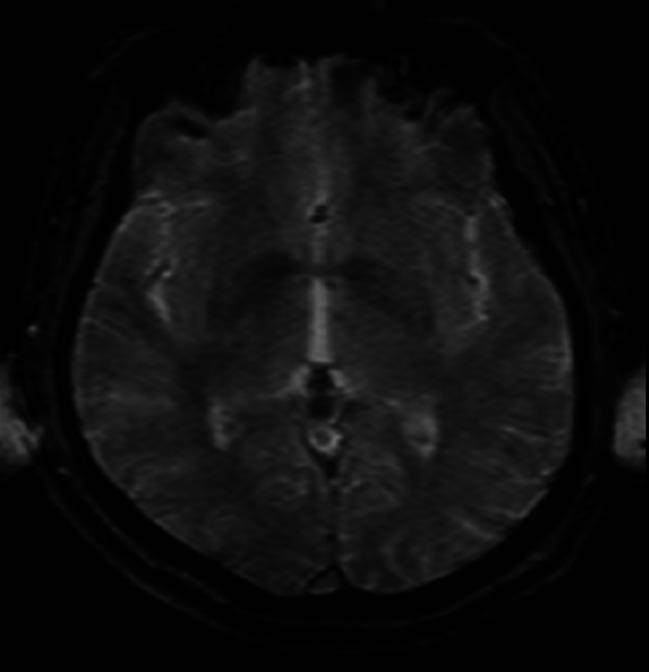

Clinical presentation: We present the clinical report of a 42-year-old male who, after a car accident, exhibited core symptoms of PTSD along with symptoms of self-organization disorders. While these symptoms persisted, the patient developed dissociative amnesia years after the trauma. Neuroimaging studies, psychometric tests, reviewed hospital records, and clinical interviews were conducted to speculate on the differential diagnosis of organic psychiatric conditions and potential diagnoses. The possible relationship between dissociative amnesia and complex post-traumatic stress disorder was examined.